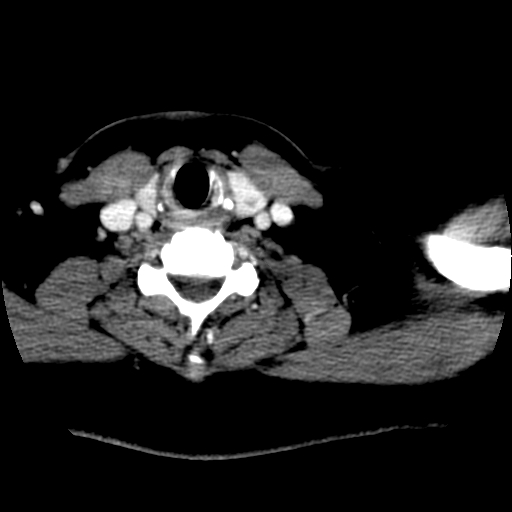

标题: CT25491:女,55岁,发现左侧甲状腺肿块一个月。 [打印本页]

女,55岁,发现左侧甲状腺肿块一个月,彩超示:甲状腺多发结节伴左叶结节液化。

考虑右叶结节性甲状腺肿,伴左叶钙化。主要(1)密度均匀,边境清。(2)病灶与血管界限清。

边界清,无明显强化,考虑考虑甲状腺腺瘤